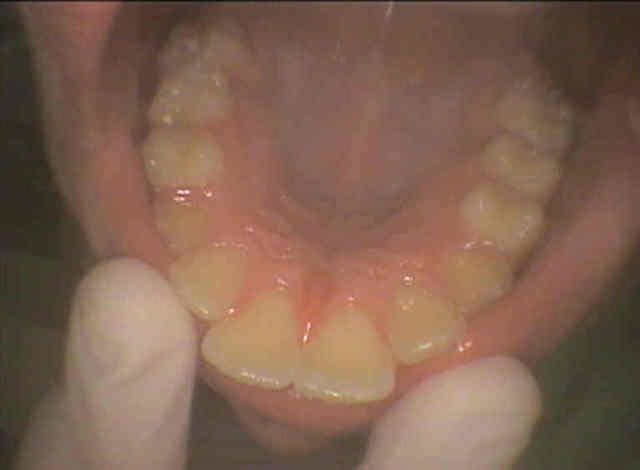

Pourriez vous me donner un avis : patient de 13 ans , le traitement odf proposé est extractions des 4 PM et des 8.

Sans relancer un nouveau debat entre écoles opposées , y a t'il unanimité quand à la pertinence du traitement proposé ?

les photos proposées sont de qualité.... plus que faible